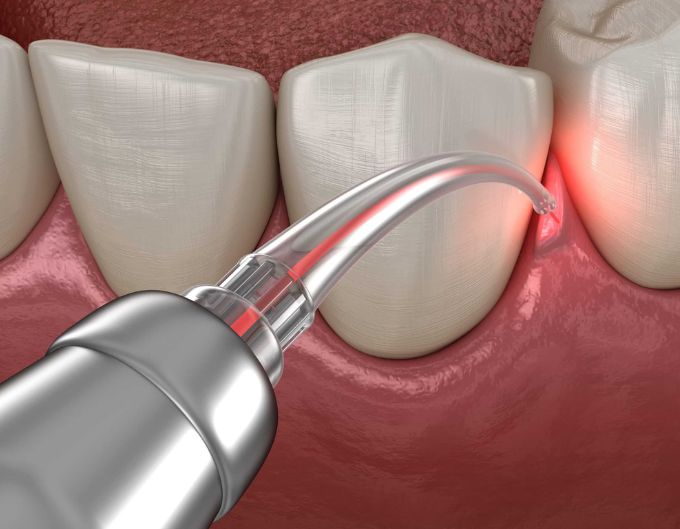

Laser Gum Surgery